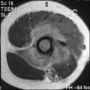

Kemik üreten selim bir kemik tümörüdür. Sıklıkla 10 - 20 yaşları arasındaki erkeklerde görülür. Ana şikayet zonklayıcı, genellikle geceleri artan ve uykudan uyandırabilen, aspirin ile geçebilen bir ağrıdır. Bazı hastalar, ağrı nedeni ile uzvunu kullanamama, buna bağlı eklem hareket kısıtlılığı ve şekil bozukluğu (kontraktür), uzuvda incelme, omurgada eğrilik gibi şikayetler ile başvurur. En sık femur boynunda ve tibiada olmakla birlikte tür kemiklerde ortaya çıkabilir. Lezyonun karakteristik özelliği düz grafide litik görülen bir çekirdek (nidus) ve bunun etrafında yoğun kemik oluşumu ile karakterize sklerotik bir halkadır. MRG, nidus çevresinde ve bazen yumuşak dokuya taşan ödemi abartarak gösterdiği için çoğu zaman daha korkutucu tanıları düşündürebilir. Sintigrafi odaksal bir tutulum ve ortasında tutulum olmayan bir nokta gösterecektir. Osteoid osteoma için en değerli ve hassas tanı koydurucu yöntem, bilgisayarlı tomografidir. İnce kesitli (en fazla 2 mm) BT incelemesinde nidus ve çevresindeki skleroz tipik olarak gösterilebilir.